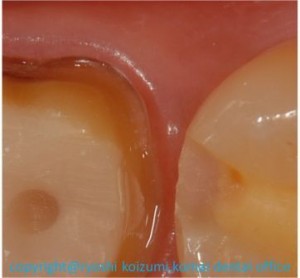

図4 ここで今日のテーマですが、患者さんからは見えない所がこの

写真の部分です。

ここで見ていただきたいのは、歯と歯肉の境目部分です。

歯が滑らかではっきりとした曲線で削ってあるのが見えますね。

実は我々専門家にとって技術の上手下手を判断できるわかりやすい

指標の1つがこの「支台歯形成」そして「マージンライン」です。

簡単にいえば、「支台歯形成」とは歯を規格通りに削ること、

「マージンライン」は削った部分と削っていない部分の境目のことで、

これがいかに滑らかで綺麗かが、その後の治療の成否に大きく影響します。

歯科医師の技術の見せ処ですから相当に気を使います。

実際、私の修業時代において、この技術の習得には膨大な時間を

かけました。

作業精度は20~50μm(0.02~0.05mm)の世界ですから

当たり前ですね。

歯科医師9年目を迎えた今ではすっかり慣れた技術ですが、

この場面になると今でもとりわけ神経を集中させています。

今みなさんはネットで写真を見ていますが、口の中はもっと暗く、そして

こんなにはっきりとは見えませんし、ここまで細部をチェックすることも

「肉眼」では不可能です。

なぜなら、肉眼では、条件が良くても0.1mm、通常は0.2mm

(100~200μm)レベルが限界です。

拡大鏡と肉眼とでは精度がいかに違うかがお分かりかと思います。

唾液や水ですぐに歯の表面が反射したり光が屈折して見えづらかったり、

照明の光が届かなくて、よく見えないことも起こります。

なにより、患者さんがずっと口を開け続けていることも大変ですから、

手際良くもなければならず、じーーっと見ている時間を確保するのも

一苦労です。

参考までに、写真の大きさは、私が愛用しているサージテル社の5倍の拡大鏡を通してのものとだいたい同じレベル、とお考えください。